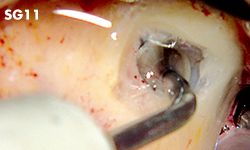

Nivelación de la cresta alveolar o escisión ósea.

Eliminación de tejido de granulación de la zona de extracción.

• POTENCIA [SURG] 80%

• Revestimiento de TiN

• Punta con borde de espátula redondeada

• Instrumento de un solo filo